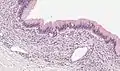

| Micrograph showing a mucinous cystadenoma of the ovary. H&E stain. | |

Mucinous cystadenoma is a benign cystic tumor lined by a mucinous epithelium. It is a type of cystic adenoma (cystadenoma).

Benign mucinous cystadenomas compose 80% of mucinous ovarian tumors[2] and 20–25% of benign ovarian tumors overall. The peak incidence occurs between 30 and 50 years of age. Benign tumors are bilateral in 5–10% of cases.